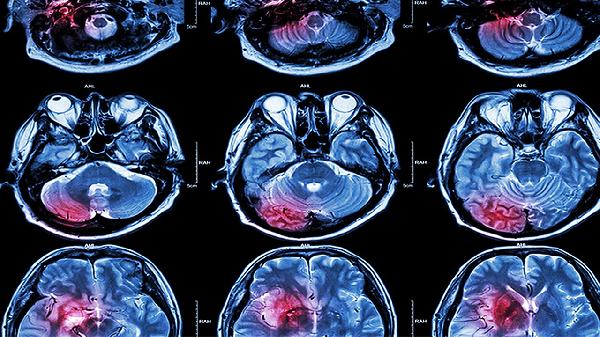

頭發(fā)麻木不一定是腦血栓,可能與神經(jīng)壓迫、頸椎病、局部血液循環(huán)障礙、焦慮癥、偏頭痛等因素有關(guān)。腦血栓引起的麻木通常伴隨肢體無力、言語障礙等癥狀。

頸椎退行性變可能刺激頸神經(jīng)根,引發(fā)頭皮放射狀麻木感。常伴隨頸部僵硬、頭暈等癥狀。建議進(jìn)行頸椎磁共振檢查,治療包括牽引、紅外線理療,藥物可選甲鈷胺片、維生素B1片等營養(yǎng)神經(jīng)藥物。